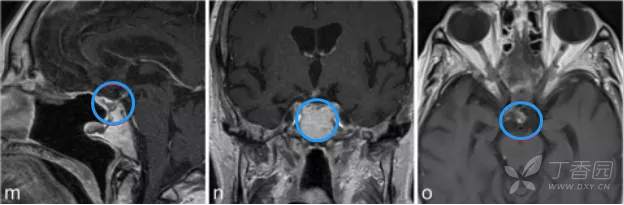

m-o图显示,磁共振成像分期立体定向放射治疗后22个月,显示肿瘤明显缩小。病人经氢化可的松和甲状腺激素的替代治疗恢复良好。